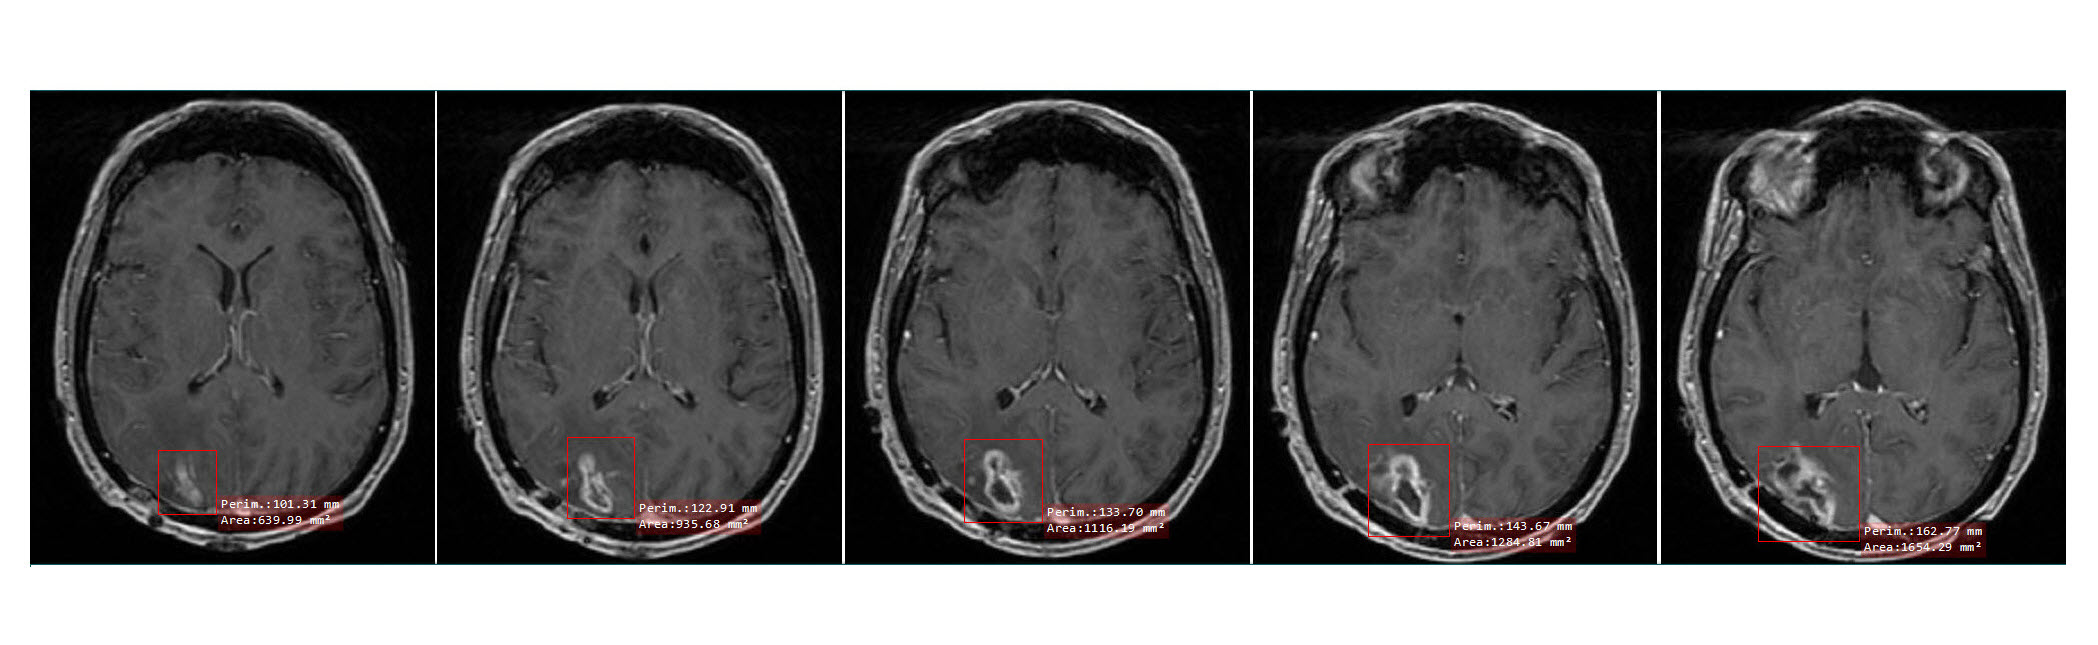

Fig.2 shows a sample sequence of dataset for one patient for 5 consecutive slices (Axial T1 GD enhanced MRI). Also, a sample image for each tumor grade for the same dataset is shown in Fig.3. It is obvious from Fig.2 and Fig.3, that while there isn’t significant interclass variation among the tumors, there exist notable intraclass difference among them; which makes the detection of tumors a challenging task even for experts.